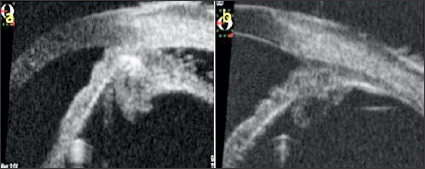

As a result of the examinations, traumatic cyclodialysis induced hypotoniamaculopathy was diagnosed for right eye. Topical corticosteroid and cyclopentolate therapy was initiated, and 3 days later the right eye axis was measured as 22,80 and the refraction rate was measured as +0,75. The IOP returned to 18 mmHg and the VA was 10/10. Comparing the OCT images taken at the end of treatment with the first received OCT, the choroid, RPE and wavy appearance of the retina (Figure 1a). Were seen to be healed at the end of treatment (Figure 1b). Cyclodialysis was detected in the temporal quadrant (Figure 2a). By UBM and normal culinary anatomy was obtained at the end of the treatment (Figure 2b). There was a normal appearance at the end of the treatment (Figure 3a), while significant increase in tortuosity was observed in vascular structures at the first examination of the FOF (Figure 3b).

Figure 2: a. Temporal quadrant UBM images of the right eye at first and b. At the end of treatment.